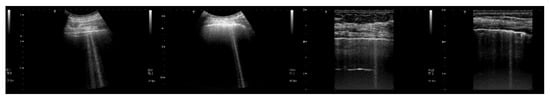

Figure 7, from left to right, shows the details of the artifacts which were obtained on agar cusps with a thickness t equal to 2, 1, 0.5, 0.3, and 0.1 mm, respectively. A distance of about 4 mm, between the upper polyethylene film and the first reflection generated by the agar cusps, is derived from the figure. This means that the US pulse, once it has been transmitted to the ridge of the agar cusps, propagates through the agar sample and reaches the lower polyethylene film before being reflected towards the probe. Figure 7 shows how modulated B-lines are obtained when the thickness t of the coupling section is equal to 0.5, 0.3, and 0.1 mm, and how confused artifacts are obtained when the latter increases. A slightly confused modulation was obtained when the thickness of the cusp ridge was equal to 1 mm. Modulated artifacts, such as those observed in cardiogenic pathologies, are finally obtained for the first time on deterministic phantoms, and they seem to be correlated to the size of the acoustic channel which links the acoustic trap to the chest wall.

Figure 7. From left to right, the figure shows the vertical artifacts which were obtained with models of agar cusps having a thickness t of the upper part equal to 2, 1, 0.5, 0.3, and 0.1 mm, respectively. The two thick white lines at the top and at the bottom of the images represent the reflection of the upper polyethylene film and its replica, respectively.

Figure 8 shows four lung US images which have been selected from a data set previously acquired by means of a Toshiba Aplio XV scanner. The two images on the left were acquired with a PVT-375BT convex probe and a central frequency equal to 6 MHz. The two images on the right were acquired with a PLT-704AT linear probe and a central frequency of 7.2 MHz. From left to right, the first image shows two B-lines; the first B-line does not show any modulation, while the second shows a slightly confused modulation. The second image shows a modulated B-line and the third shows a non-modulated B-line. The last image on the right shows a modulated B-line. An analogy with the experimental results illustrated in Figure 7 emerges, and the physicians’ hypothesis regarding the progression of a lung disorder supports this thesis. According to their hypothesis, the interstitial spaces between the alveoli gradually increase with the progression of a pathology, and the modulated B-lines are related only to the early stages of the pathology.

Figure 8. From left to right, the first image shows two B-lines; the first B-line does not show any modulation, while the second shows a slightly confused modulation. The second image shows a modulated B-line, and the third shows a non-modulated B-line. The last image on the right shows a modulated B-line.